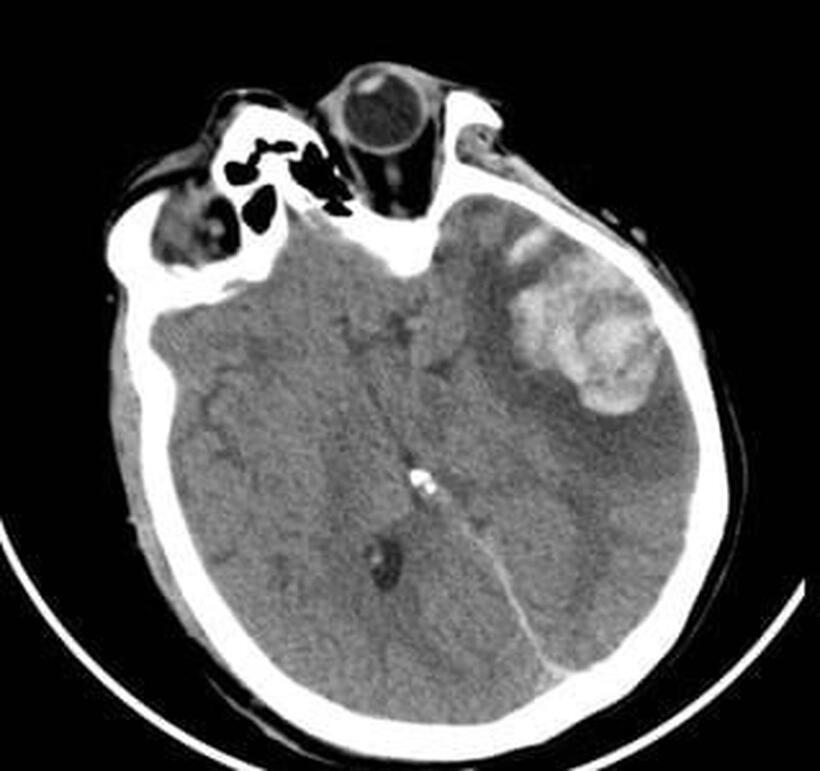

Phim CT scan ngày 06/01/2026 người bệnh G.N. cho thấy vùng dập não xuất huyết thái dương lớn kèm phù tổ chức xung quanh. Ảnh: Bệnh viện Nhân dân 115.

Cùng thời điểm, bà G.N. (53 tuổi), mẹ của anh G.A., cũng nhập viện trong tình trạng lơ mơ, dập não thái dương lượng lớn. Các bác sĩ đã quyết định điều trị bảo tồn thay vì phẫu thuật để tránh tổn thương thứ phát.

Quyết định này đã mang lại hiệu quả tích cực, bà G.N. dần tỉnh táo và cải thiện chức năng ngôn ngữ. Sau 10 ngày điều trị tại khoa Ngoại Thần kinh, bà đã hồi phục và được xuất viện.